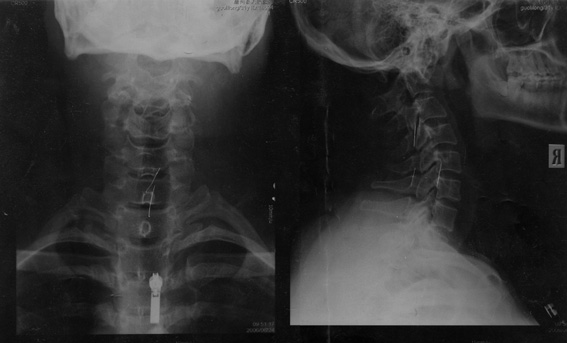

以下是x片:

从x光片看.环枢椎错位可能性大.建议照环枢椎张口位片或做ct